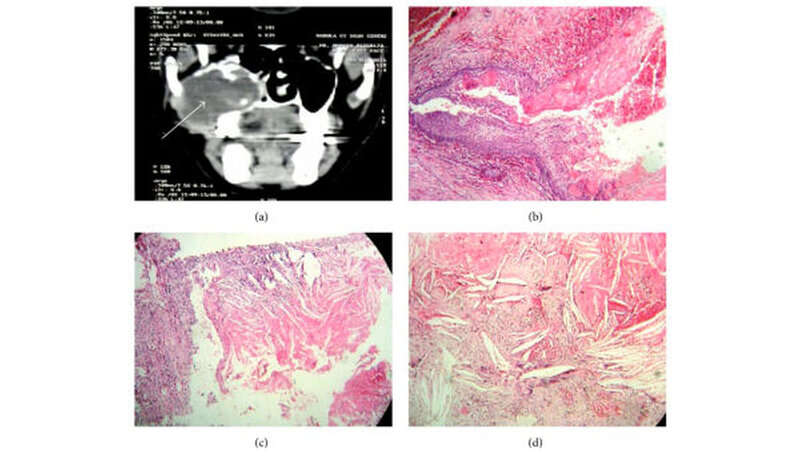

Eine 38-jährige Frau klagte seit sechs Monaten über eine Schwellung im rechten Unterkieferseitenzahnbereich. Sie gab an, dass die zum Zeitpunkt der Untersuchung 3 x 2 cm große Schwellung progredient gewachsen, aber nicht schmerzhaft sei. Die Schleimhaut erschien glatt blande. In der Orthopantomografie wurde eine klar definierte Radioluzenz regio 48 gesehen. Bei Verdacht auf Vorliegen eines KCOT fand die chirurgische Enukleation der Zyste statt, wobei in der histologischen Beurteilung wiederum reichlich Cholesterinkristalle in der zystischen Kapsel in Verbindung mit mehrkernigen Riesenzellen gefunden werden konnten. Daraufhin wurde die Diagnose einer follikulären Zyste mit Cholesterolgranulom gestellt (Abbildung 2).

Ein 47-jähriger Mann klagte seit zwei Tagen über Schmerzen im linken Unterkieferseitenzahnbereich, wobei er dort bereits seit zwei Monaten an einer progredient wachsenden Schwellung gelitten hatte. Während die klinische Untersuchung lediglich eine wenig ausgeprägte Schwellung ergab, konnte via Computertomografie eine demarkierte Radioluzenz von 3 x 1,4 cm nachweisen. Eine Inzisionsbiopsie ergab das histologische Korrelat einer follikulären Zyste, während das endgültige Operationspräparat nach der vollständigen Entfernung Cholesterinkristalle zusammen mit einem chronisch entzündlichen Zellinfiltrat aufwies (Abbildung 3). Auch hier konnte daher die Diagnose einer follikulären Zyste mit Cholesterolgranulom gefällt werden.